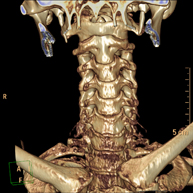

- Cervical spine CT

Radiological test that provides high definition anatomical images of the cervical vertebrae using CT (Computed Tomography) equipment. Indicated for: cervical pain without/with irradiation to the arms, trauma.